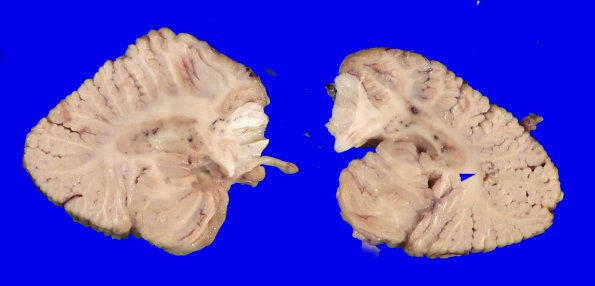

The cerebellum has several cystic foci deep in the region of the dentate nucleus.as well as involving the deep folia (arrow).